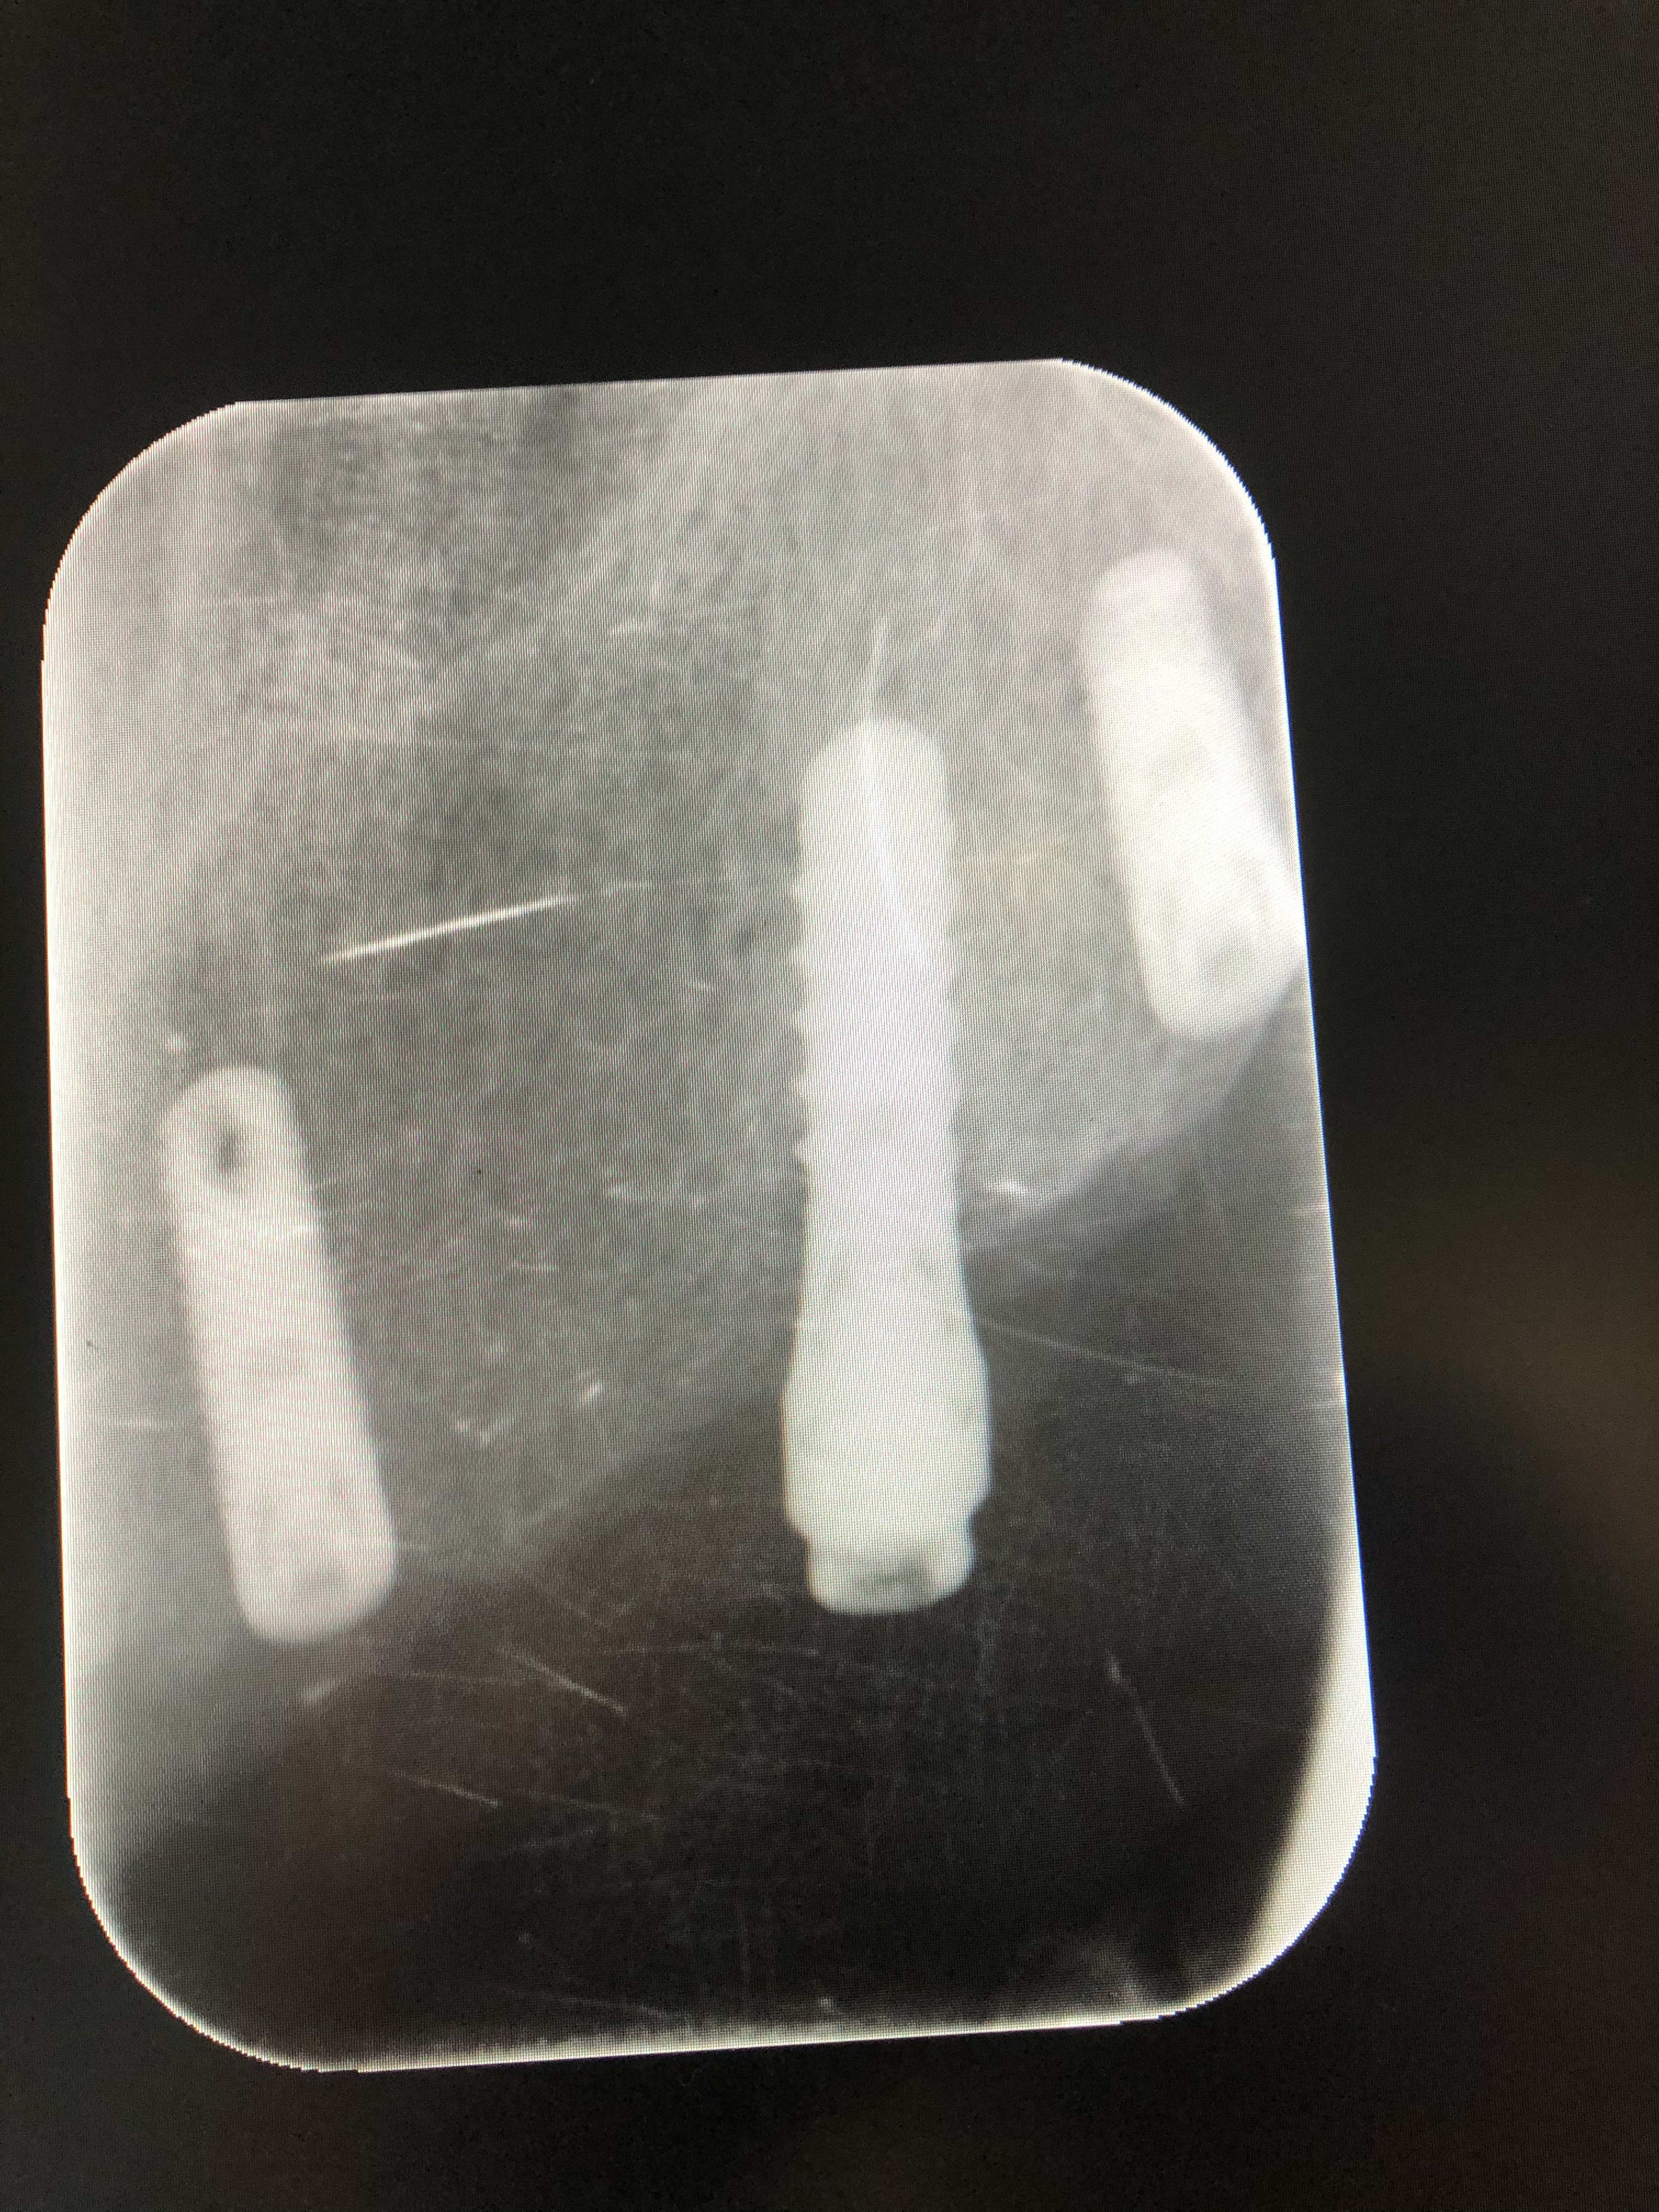

Je recherche la marque de cet implant, pouvez vous me renseigner ?

Straumann